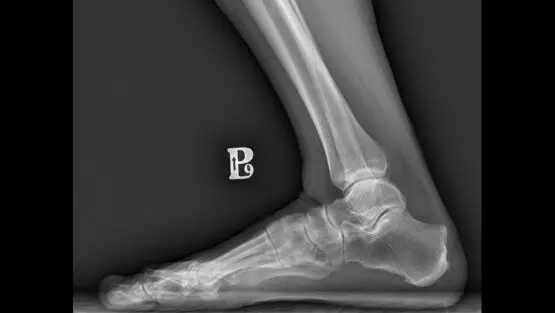

Zdjęcie RTG prawej nogi – zdrowy staw skokowy